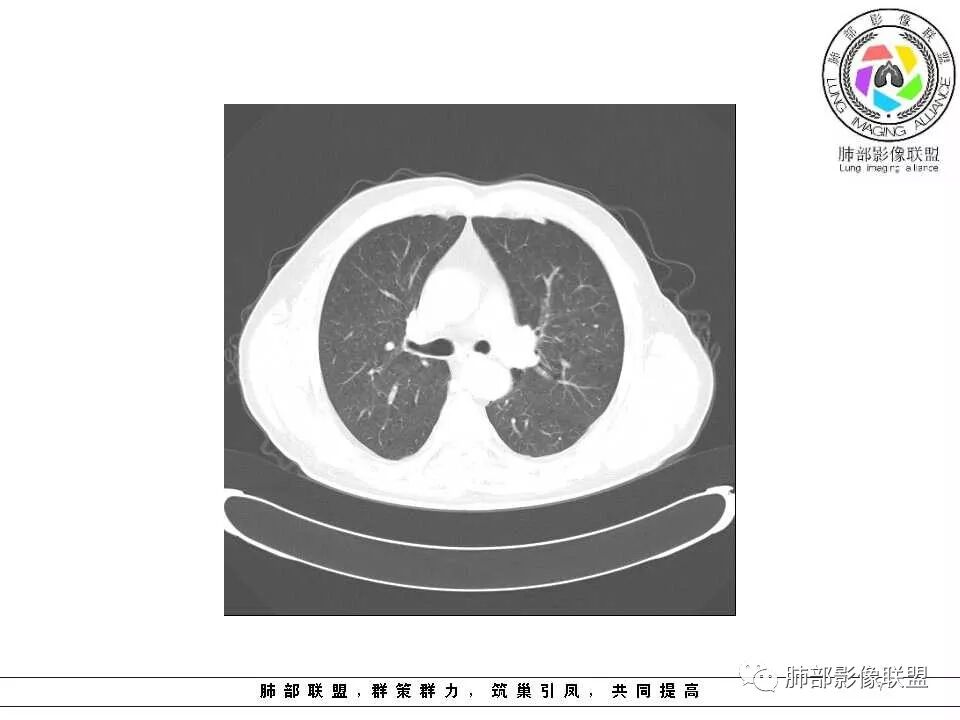

临床特点老年男性、有咯血一个月

影像学特点:肺气肿背景下在大概一年的时间里出现了一个光滑的小结节,因为图像给的不是太薄,与支气管的关系判断不清,从结节周围出现斑片状炎症来判断,应该考虑结节位于支气管内,周围是阻塞性炎症,这样比较容易解释咯血

纵隔窗上似乎结节内可见点状高密度影,同时没有明显肿大淋巴结

老年男性,肺气肿基础。约一年时间出现左肺上叶舌段支气管近端结节影,远端斑片样阴影,边缘模糊。考虑近端恶性占位,远端有阻塞性炎症。

老年男性,有咳血病史,左肺上叶舌段一年时间出现新发类圆形小结节,感觉在支气管内,部分凸出气管外,没有mpr不好说,远端肺野斑片模糊影,考虑阻塞性炎症,纵隔无明显肿大淋巴结,小细胞代排,按照发展速度,类癌低度恶性,应该发展缓慢,一年病史,代排,首先考虑鳞癌并阻塞性炎症

肺气肿背景,2016年左肺上叶上舌段见微结节,2017年5月左肺结节增大,密度均匀,边缘光滑锐利,与邻近血管关系密切,血管贴壁走行,外侧见尖状突起,下舌段片状影,沿着支气管走行,内有粘液栓,考虑鳞癌,鉴别小细胞肺癌。

肺气肿背景,2016年左肺上叶上舌段见微结节,一年后左肺结节增大,密度均匀,边缘光滑、膨隆,似见小分叶,下舌段片状影,沿着支气管走行,内,老年患者,咯血1月。考虑恶性病变并阻塞性肺炎,鳞癌?注意鉴别结核。

左肺上叶舌段支气管管壁略增厚 间隔一年 管壁增厚明显 向腔外突出形成结节 管腔闭塞 远端片状及斑片影 纵隔淋巴结增大 肺气肿背景 考虑鳞癌伴阻塞性炎症可能

老年男性,咯血1月,肺气肿背景,16年左肺上叶舌段结节,左肺门疑似淋巴结肿大,呈结节感。17年左肺上叶舌段见沿支气管走行分布结节 远端阻塞性肺炎,左肺门淋巴结肿大明显,首先考虑恶性病变,鳞癌?类癌?

前次片2016年4月20相应位置就有小点状病灶,2017-5-15呈结节影改变,边界膨隆,远端阻塞炎性改变,考虑肺癌,鉴别炎性结节!

老年男性,肺气肿背景,左肺上叶舌段一年前小结节后长大,实性,与邻近气管关系密切,远端有少许小片状炎症类小结节状,左肺门淋巴结肿大,首先考虑恶性,鳞癌可能性大,代排小细胞癌。病灶下方斑片状影,考虑炎症。

前后对比,这些结节其实是没引起支气管远端病变的

南大标注,这几个确实结节没有阻塞支气管,感觉是在血管分叉地方。

@南边 关键是上面这几个结节有的密度度,有的密度低。与下面堵塞支气管的结节样改变是否不是一回事,

如果下面堵塞是恶性,那上面的是不是考虑转移?另外一年结那个疑似结节的地方与现在堵塞的地方好象不一致。